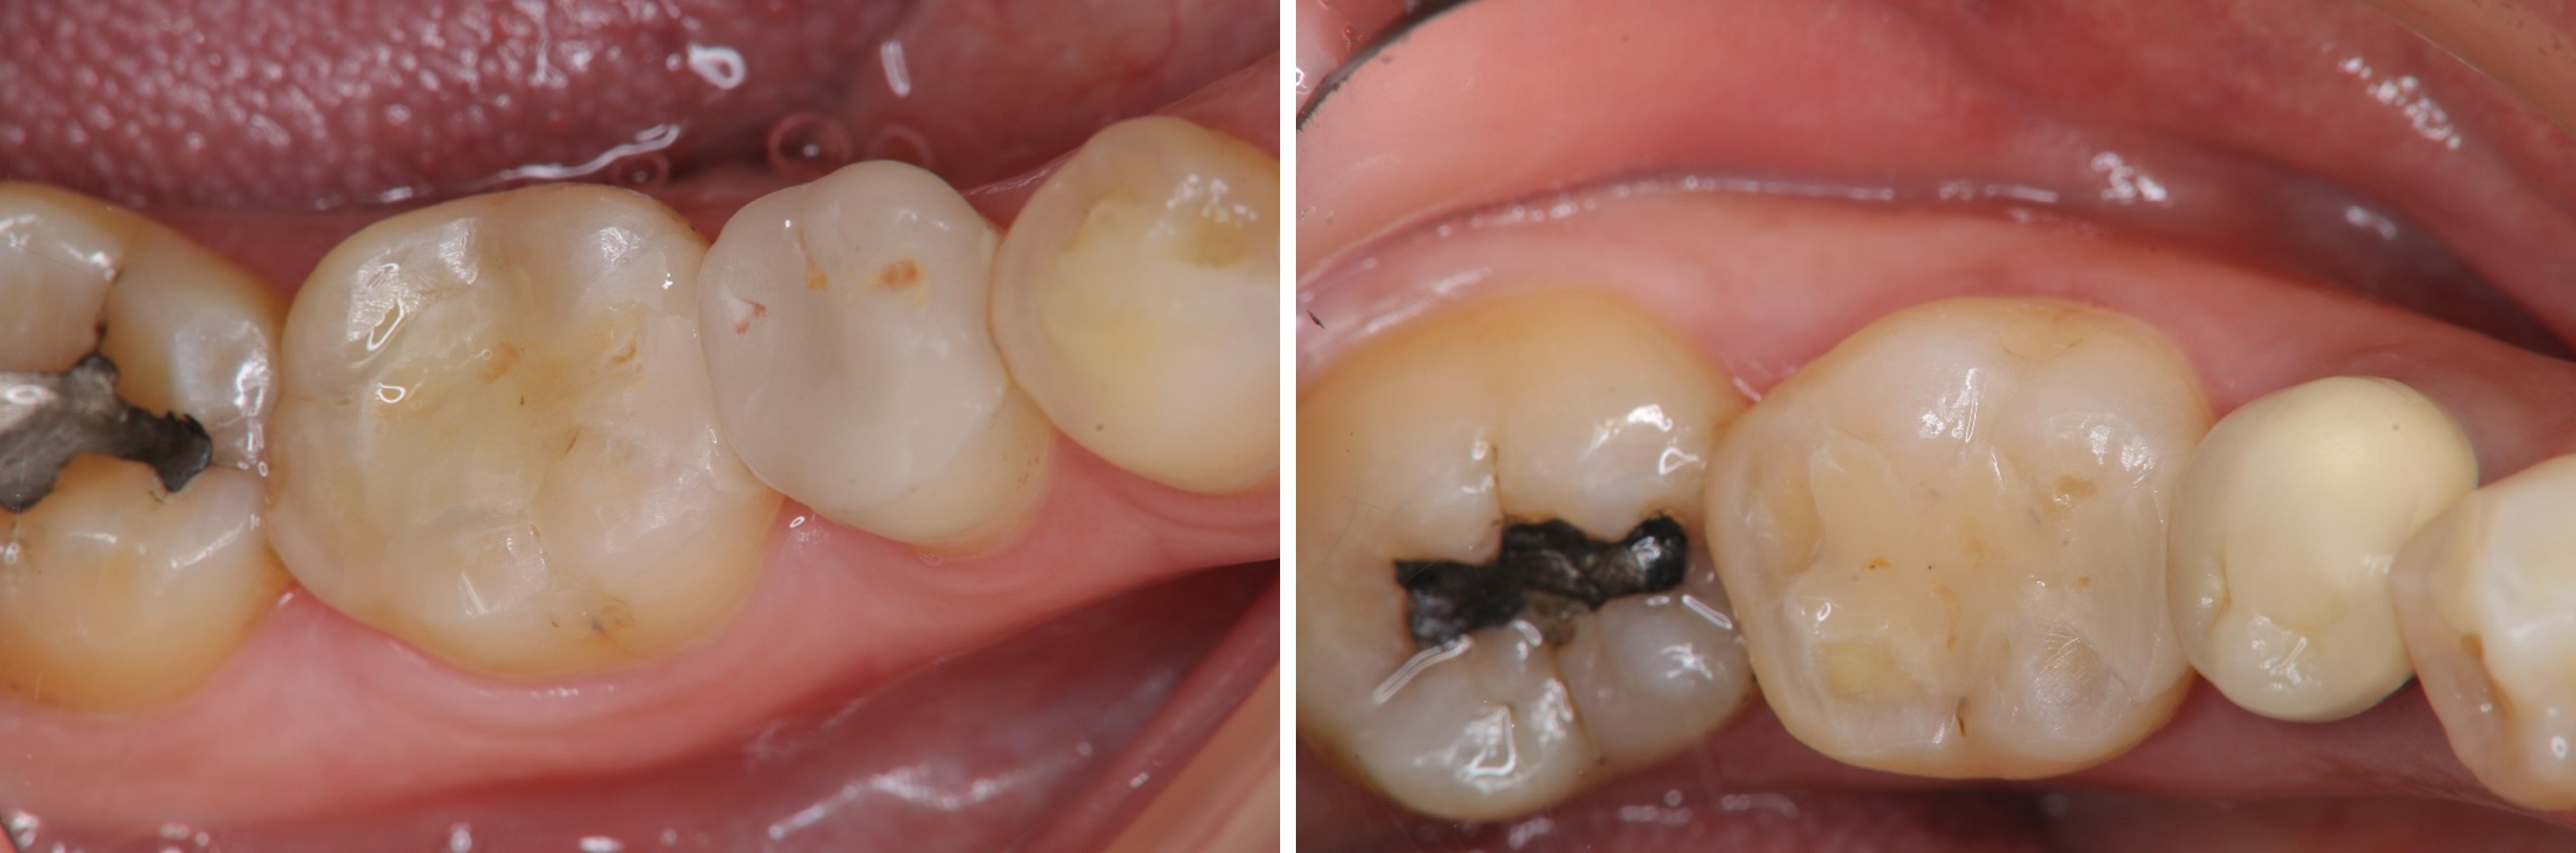

治療前,大臼齒冷熱敏感

X光可見大臼齒內有蛀洞